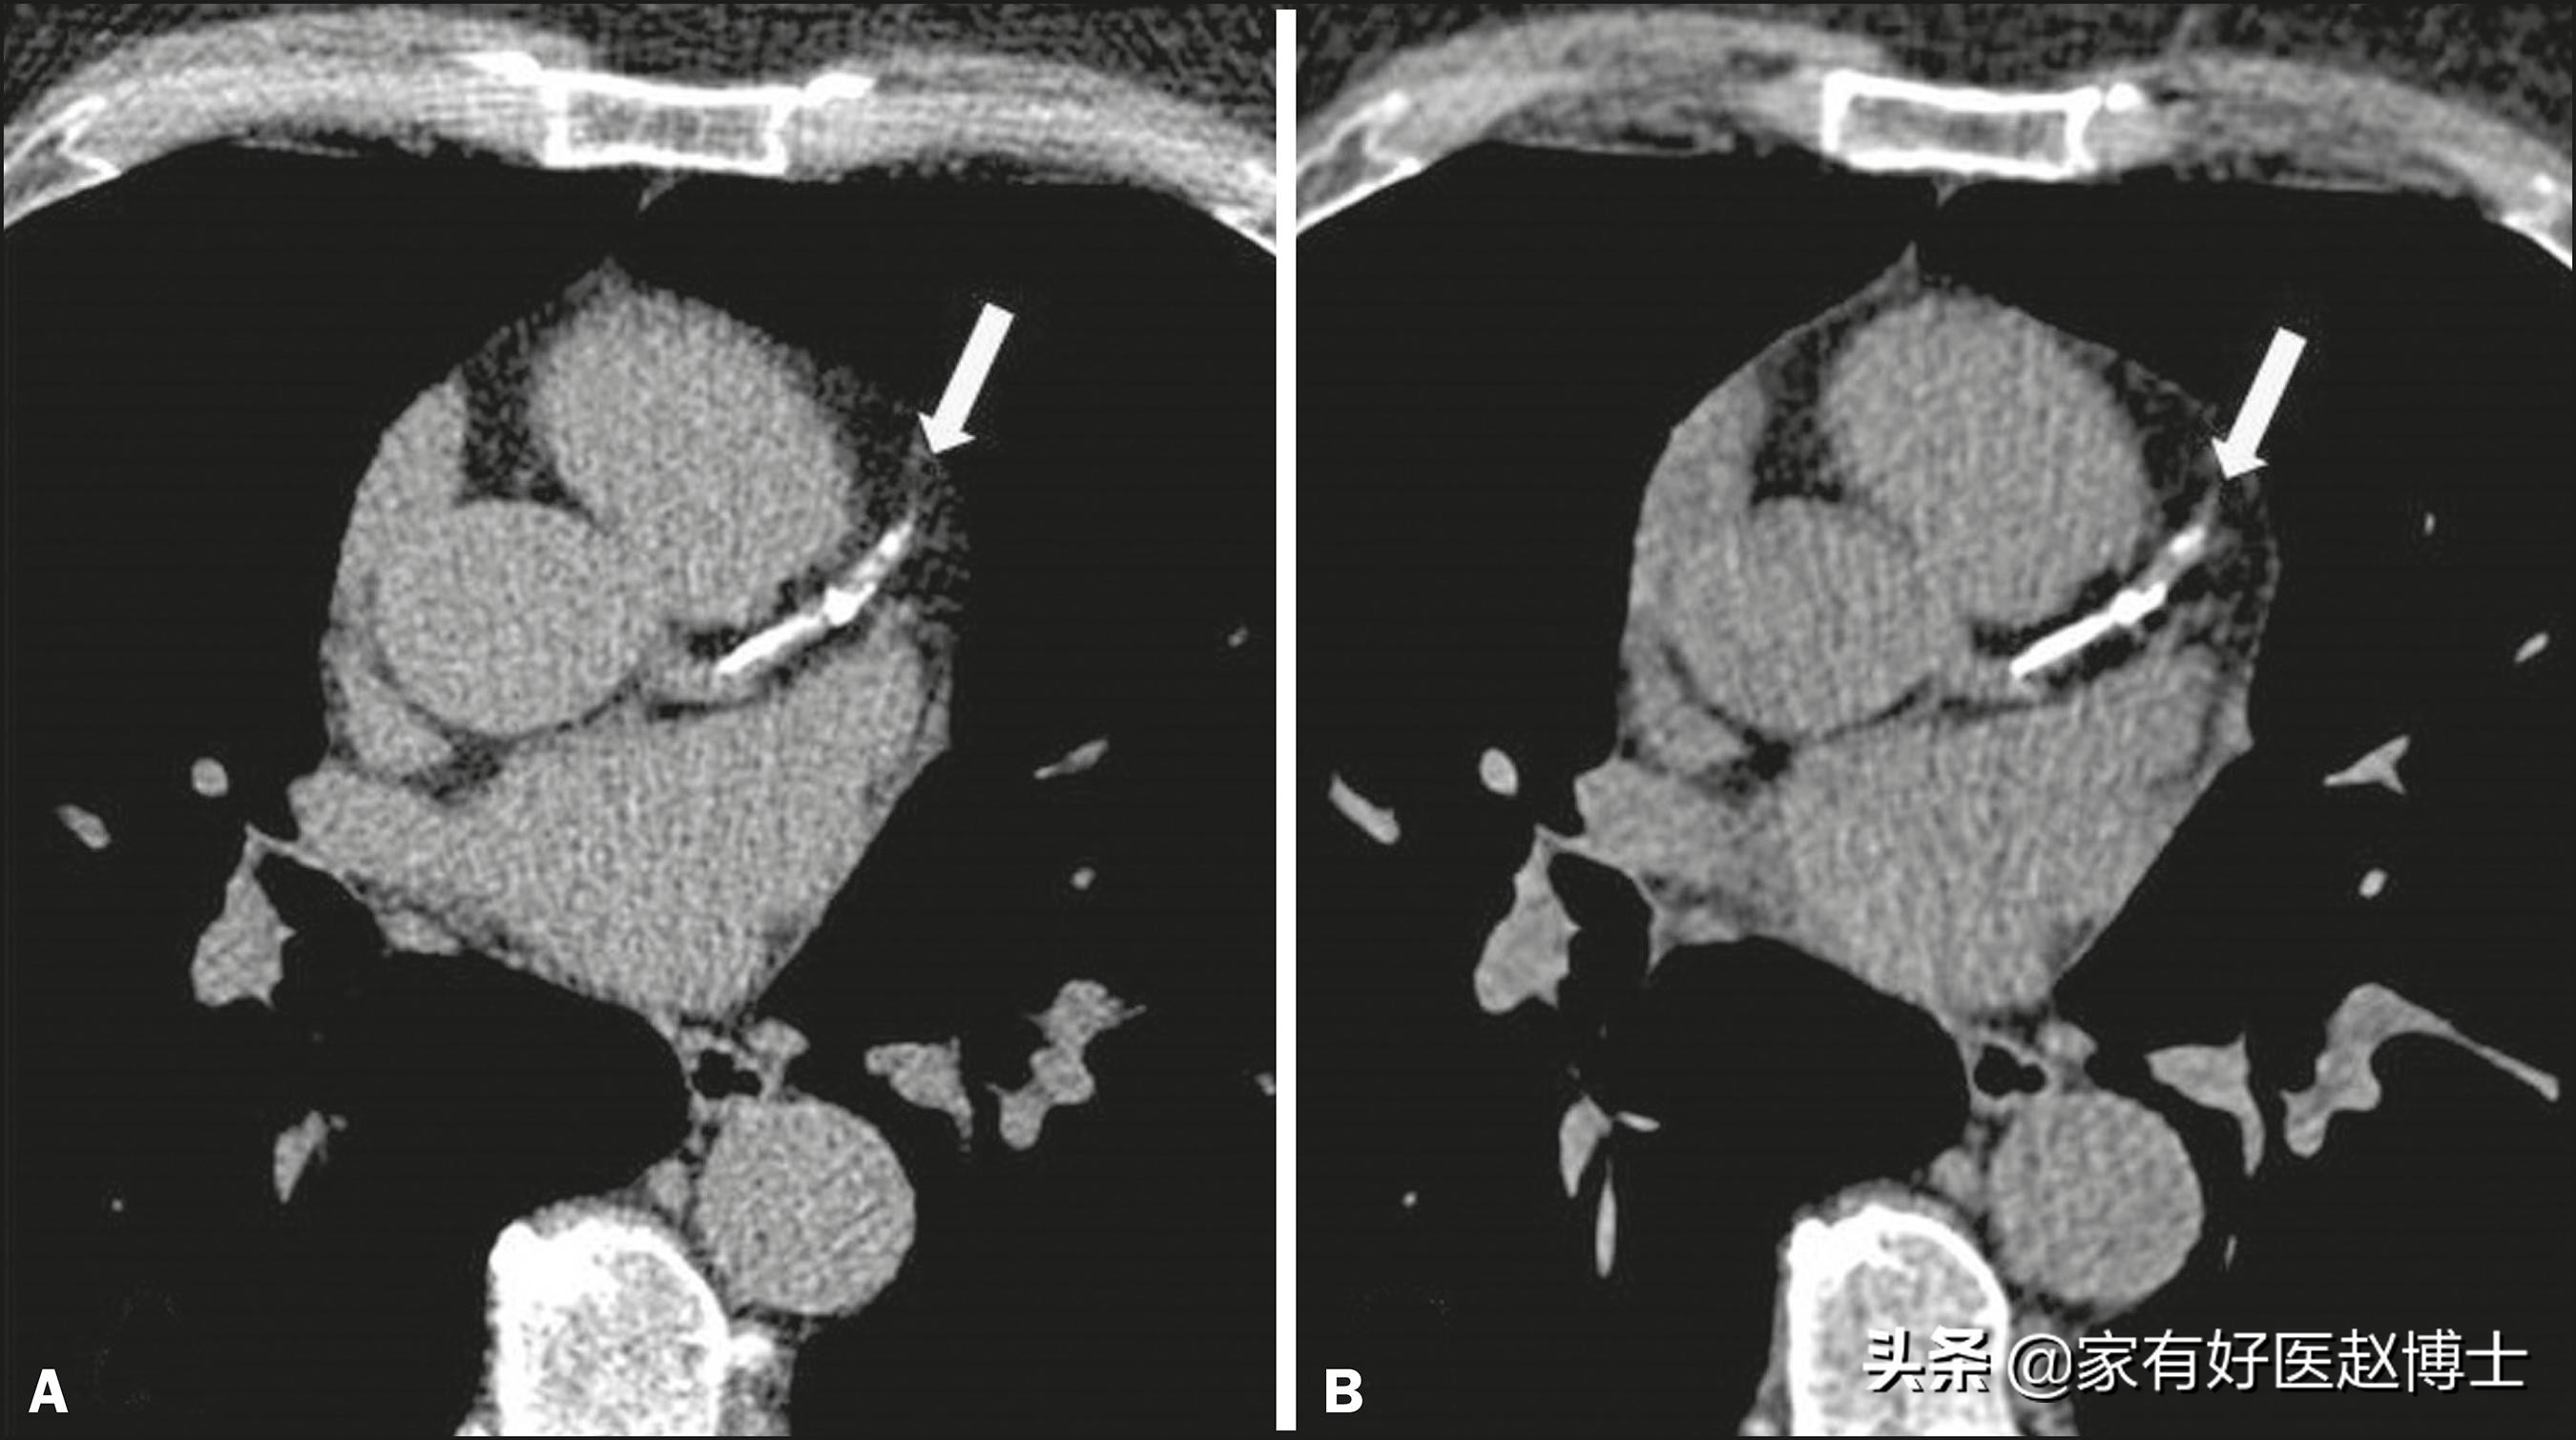

第二个要说的存在恶性风险的是乳腺钙化。目前,对乳腺钙化尤其是微小钙化,识别能力最强的检查方法是乳腺X线摄影,而不是乳腺超声。

所以,大家不要觉得体检做了乳腺超声就可以了,对于年龄超过40岁、乳腺癌风险较高的女性,最好是能够把乳腺X线摄影和乳腺超声都做一下,这样才不容易漏掉一些早期的乳腺癌征象。

乳腺的钙化征象是存在良恶性之分的,一般认为,分散的、粗大的乳腺钙化往往提示良性概率大,可能是乳腺增生、乳腺炎或乳腺导管扩张等病因引起的;而当乳腺中发现密集的、细小的钙化灶,尤其是单位面积内存在多于7~8个钙化点时,需要高度警惕乳腺癌的风险。